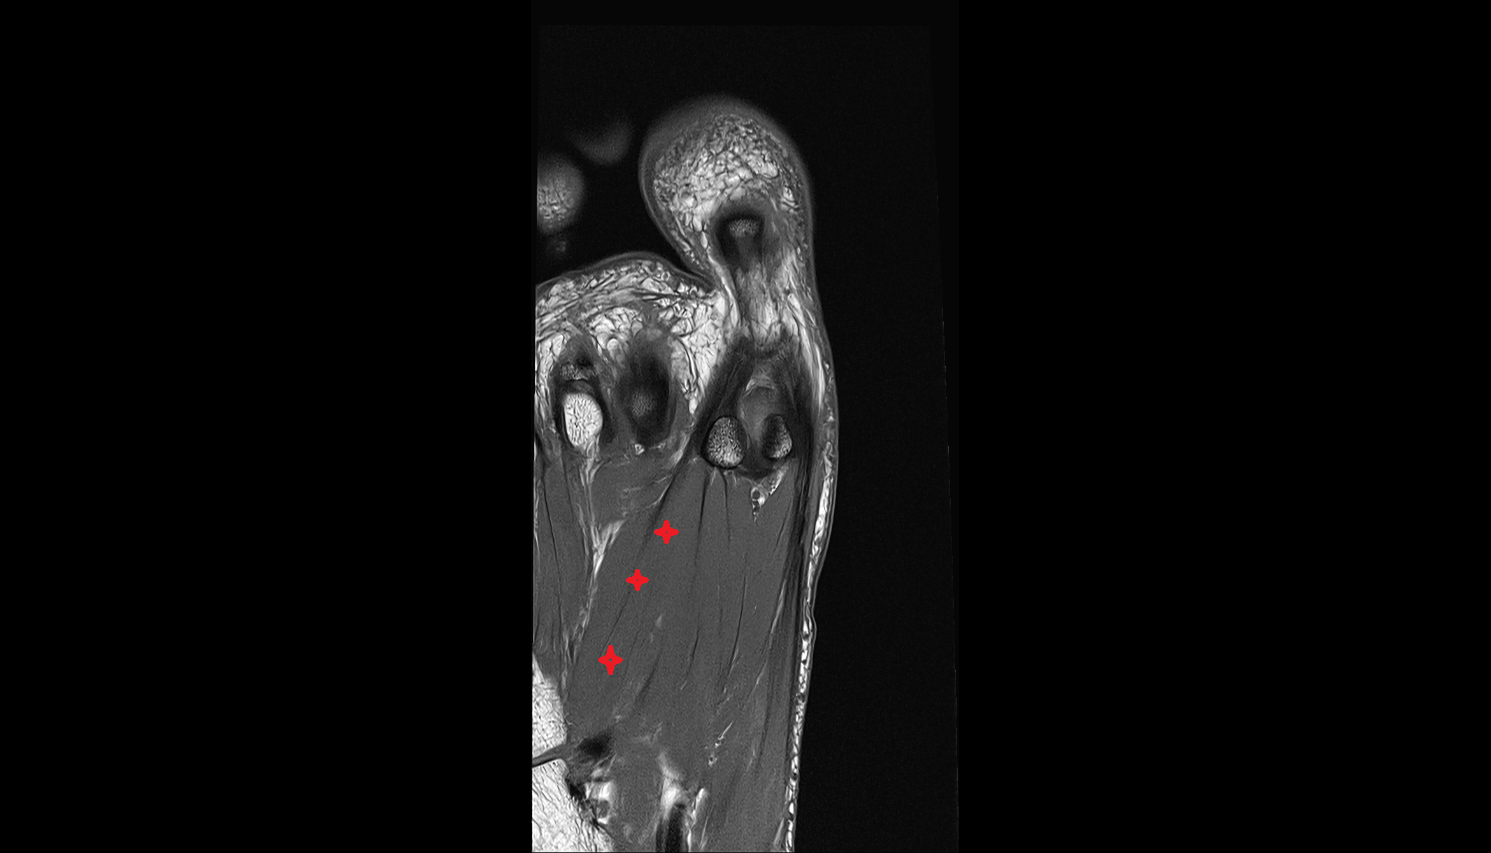

- Plantar aponeurosis